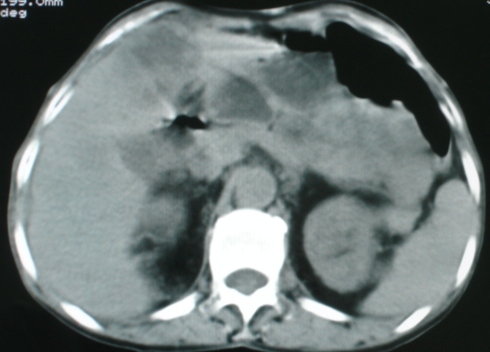

以下是引用zsl6918在2008-11-4 19:14:00的发言:[br]多发转移性改变,子宫改变不除外为原发灶